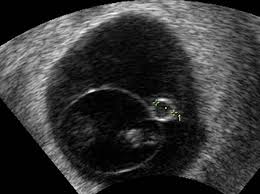

Schwangerschaftswoche sind auch die Struktur des Embryos und sein Herzschlag zu erkennen. Eine frühe Ultraschalluntersuchung dient vor allem dazu die Schwangerschaft zu bestätigen und eine Eileiterschwangerschaft auszuschließen. Die Entwicklung des Embryos schreitet nun rasant voran.

SSW Details zu Entwicklung des Babys der erste Ultraschall Schwangerschaftssymptome Tipps zur Linderung uvm. Vom Bauch des Embryos aus führt die Nabelschnur in der sich nun Blutgefäße zum Transport der Nährstoffe bilden zur Plazenta. Ist Dein Gynäkologe mit entsprechender Technik ausgestattet kann er die Schwangerschaft in der 6.

Von einer auf die andere Woche hat dein Baby seine Größe verdoppelt. SSW zum ersten Mal den Herzschlag deines Babys am Ultraschall. Im Lauf der kommenden Wochen bildet sich ein primitives Kreislaufsystem Im Verlauf der Schwangerschaft werden drei Ultraschall-Untersuchungen Ultraschall-Screening angeboten.

SSW bereits vorhanden im Ultraschall sind am Kopf die Anlagen für Augen Ohren und Gehirn zu erkennen. Im Ultraschall kann man den Puls dieser Blutgefäße beobachten.

Woche SSW 5 If playback doesnt begin shortly try restarting your device. Schwangerschaftswoche deinen ersten Ultraschall-Termin hast wirst du wahrscheinlich die Fruchthöhle und den Dottersack sehen können. Auf dem Ultraschall in der 6. Eine Ultraschalluntersuchung vor der vollendeten 6. Das ist jedoch erst mal kein Grund zur Beunruhigung. Wie geht es dir und dem Baby. Ultraschall nichts zu sehen ssw 66. Hier kann man auch feststellen ob das Baby in der Gebärmutter eingenistet ist und der Arzt kann die Schwangerschaft bestätigen. In der Regel werden Zwillinge bereits bei der ersten Ultraschalluntersuchung entdeckt die etwa in der sechsten Schwangerschaftswoche erfolgt Sie sind 5 Wochen schwanger SSW 5 oder in der 6.